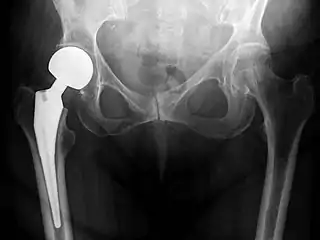

Hip replacement is a surgical procedure in which the hip joint is replaced by a prosthetic implant, that is, a hip prosthesis. Hip replacement surgery can be performed as a total replacement or a hemi/semi(half) replacement. Such joint replacement orthopaedic surgery is generally conducted to relieve arthritis pain or in some hip fractures. A total hip replacement (total hip arthroplasty or THA) consists of replacing both the acetabulum and the femoral head while hemiarthroplasty generally only replaces the femoral head. Hip replacement is one of the most common orthopaedic operations, though patient satisfaction varies widely. Approximately 58% of total hip replacements are estimated to last 25 years.[1] The average cost of a total hip replacement in 2012 was $40,364 in the United States, and about $7,700 to $12,000 in most European countries.[2]

Post-operative projectional radiography is routinely performed to ensure proper configuration of hip prostheses.

X-ray of the hips, with a right-sided hemiarthroplasty